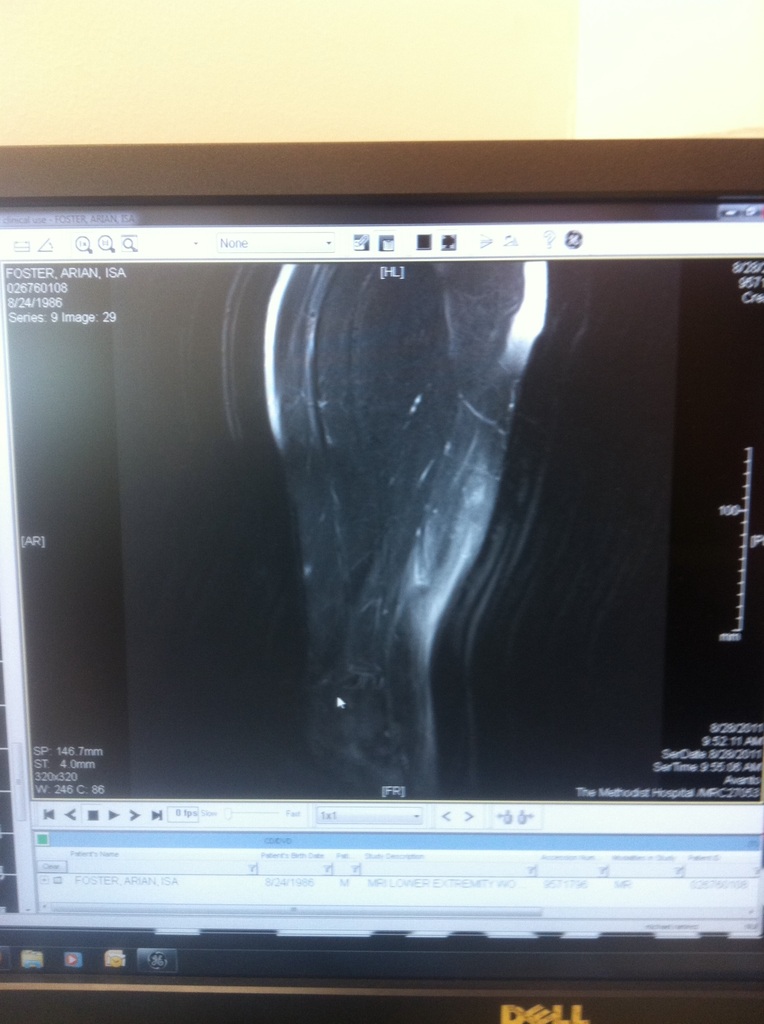

Today, in perhaps an NFL-first, a player tweeted his MRI.

Earlier today, Houston Texans running back Arian Foster tweeted the MRI image of his injured hamstring.

For those who can’t grasp Foster’s diagnosis, he offered a medical explanation:

This is an MRI of my hamstring, The white stuff surrounding the muscle is known in the medical world as anti-awesomeness.

Foster suffered the injury last Saturday night in San Francisco and is jogging lightly but according to Dr. Michael Kaplan of ESPN, he could potentially miss two to three weeks.